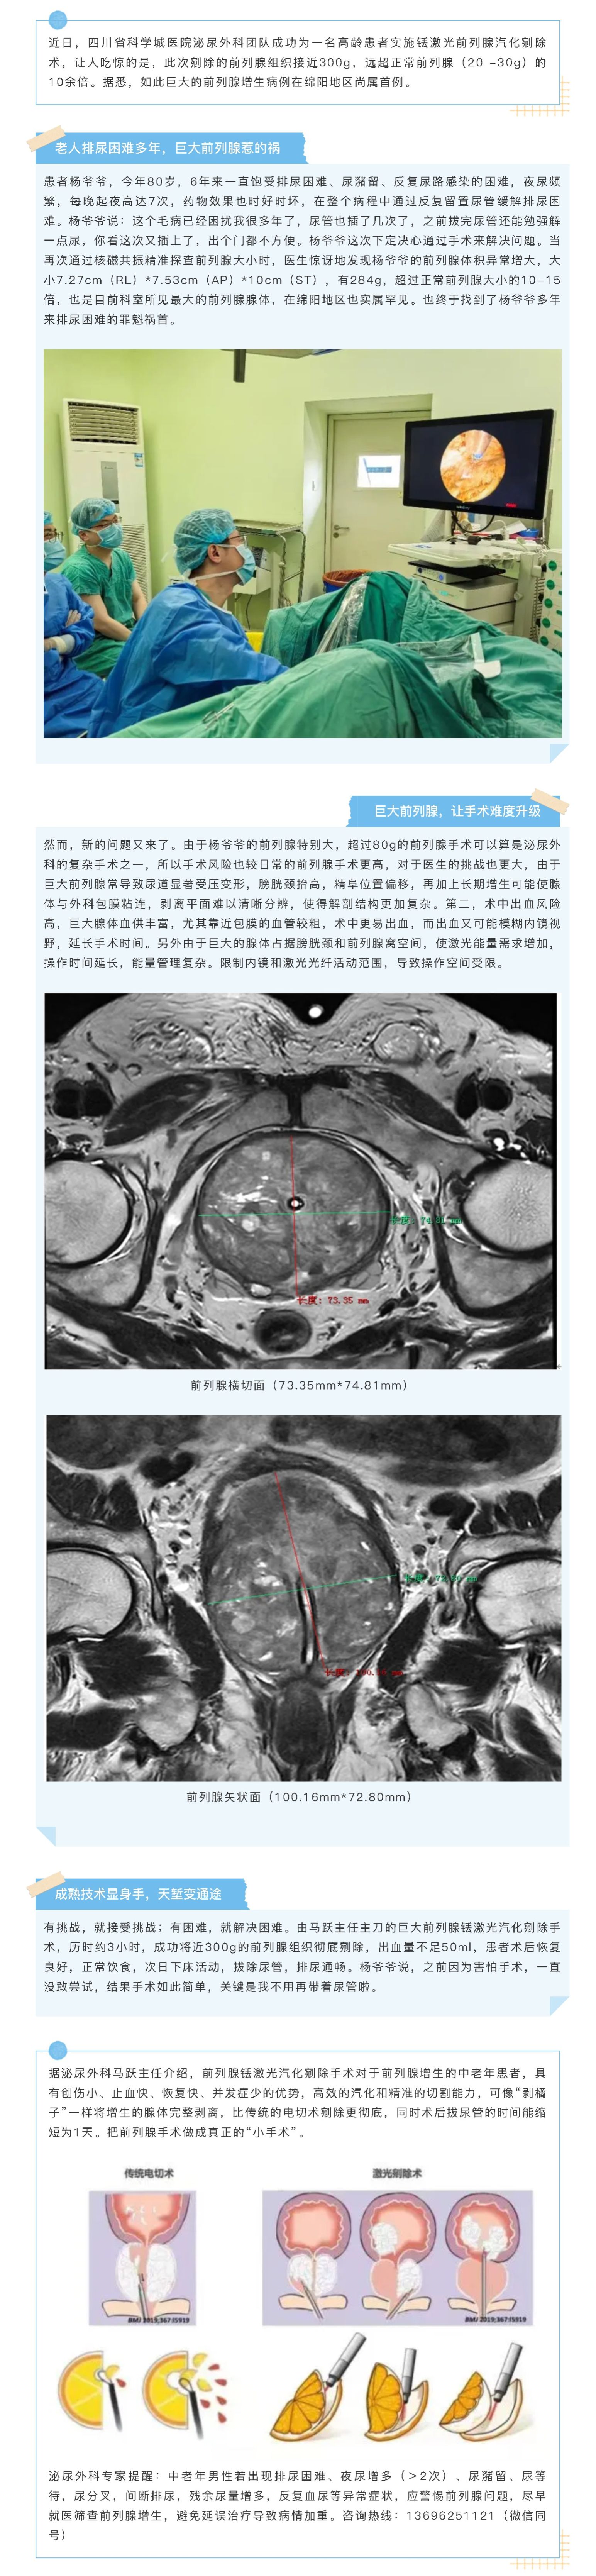

【一线传真】前列腺“消消乐”,铥激光让增生组织秒变“空气”